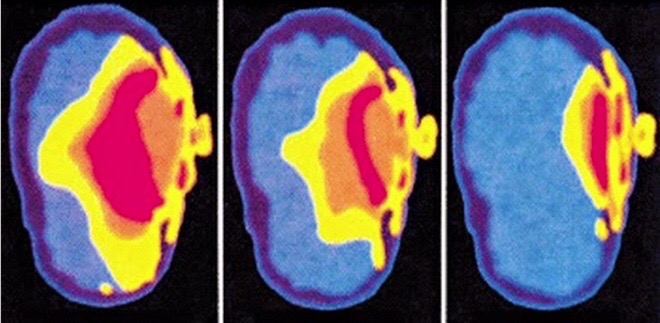

Sóng điện thoại có thể tấn công não bộ (Ảnh: Internet)